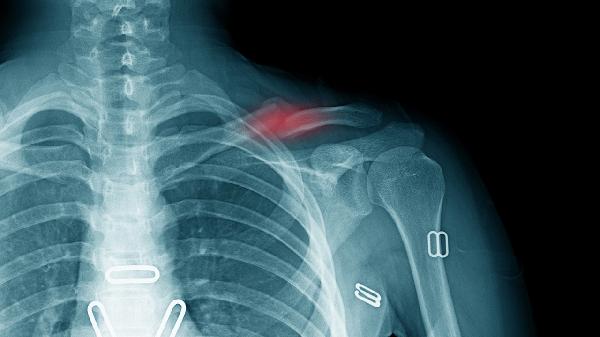

1、锁骨骨折

锁骨骨折可能导致右边锁骨下面骨头突出,通常由外伤或剧烈运动引起,伴随局部肿胀和活动受限。治疗需使用锁骨固定带制动,遵医嘱服用布洛芬缓释胶囊、接骨七厘片等药物促进愈合,严重时需手术复位。

4、胸锁关节脱位

胸锁关节脱位可导致右边锁骨下方明显突起,常见于车祸或运动损伤,伴有关节畸形和上肢功能障碍。急性期需冰敷并用手法复位,慢性脱位需手术重建韧带,恢复期使用氟比洛芬凝胶贴膏缓解疼痛。